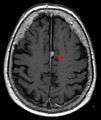

![]() Brain MRI | |